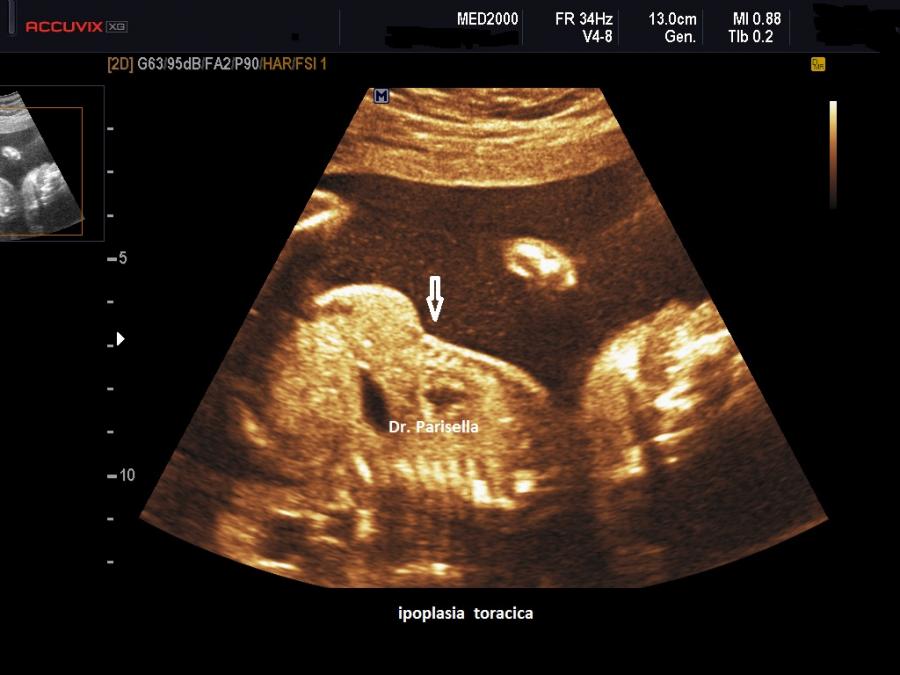

La forma grave (perinatale, infantile) è simile all'osteogenesi imperfetta tipo II con severo accorciamento degli arti (specie femore ed omero) la cui diafisi appare ricurva, ipoplasia toracica grave, ipomineralizzazione diffusa ad eccezione delle clavicole, idrope (nelle forme ad insorgenza precoce), polidramnios; incostantemente si hanno coste sottili e sedi di fratture.

MICROMELIA SEVERA, IPOPLASIA TORACICA SEVERA, IPOMINERALIZZAZIONE ESTREMA TRANNE LE CLAVICOLE, IDROPE (evidente principalmente nei casi a riscontro precoce), DEFORMAZIONE DELLA VOLTA CRANICA ALLA COMPRESSIONE IMPRESSA DALLA SONDA.